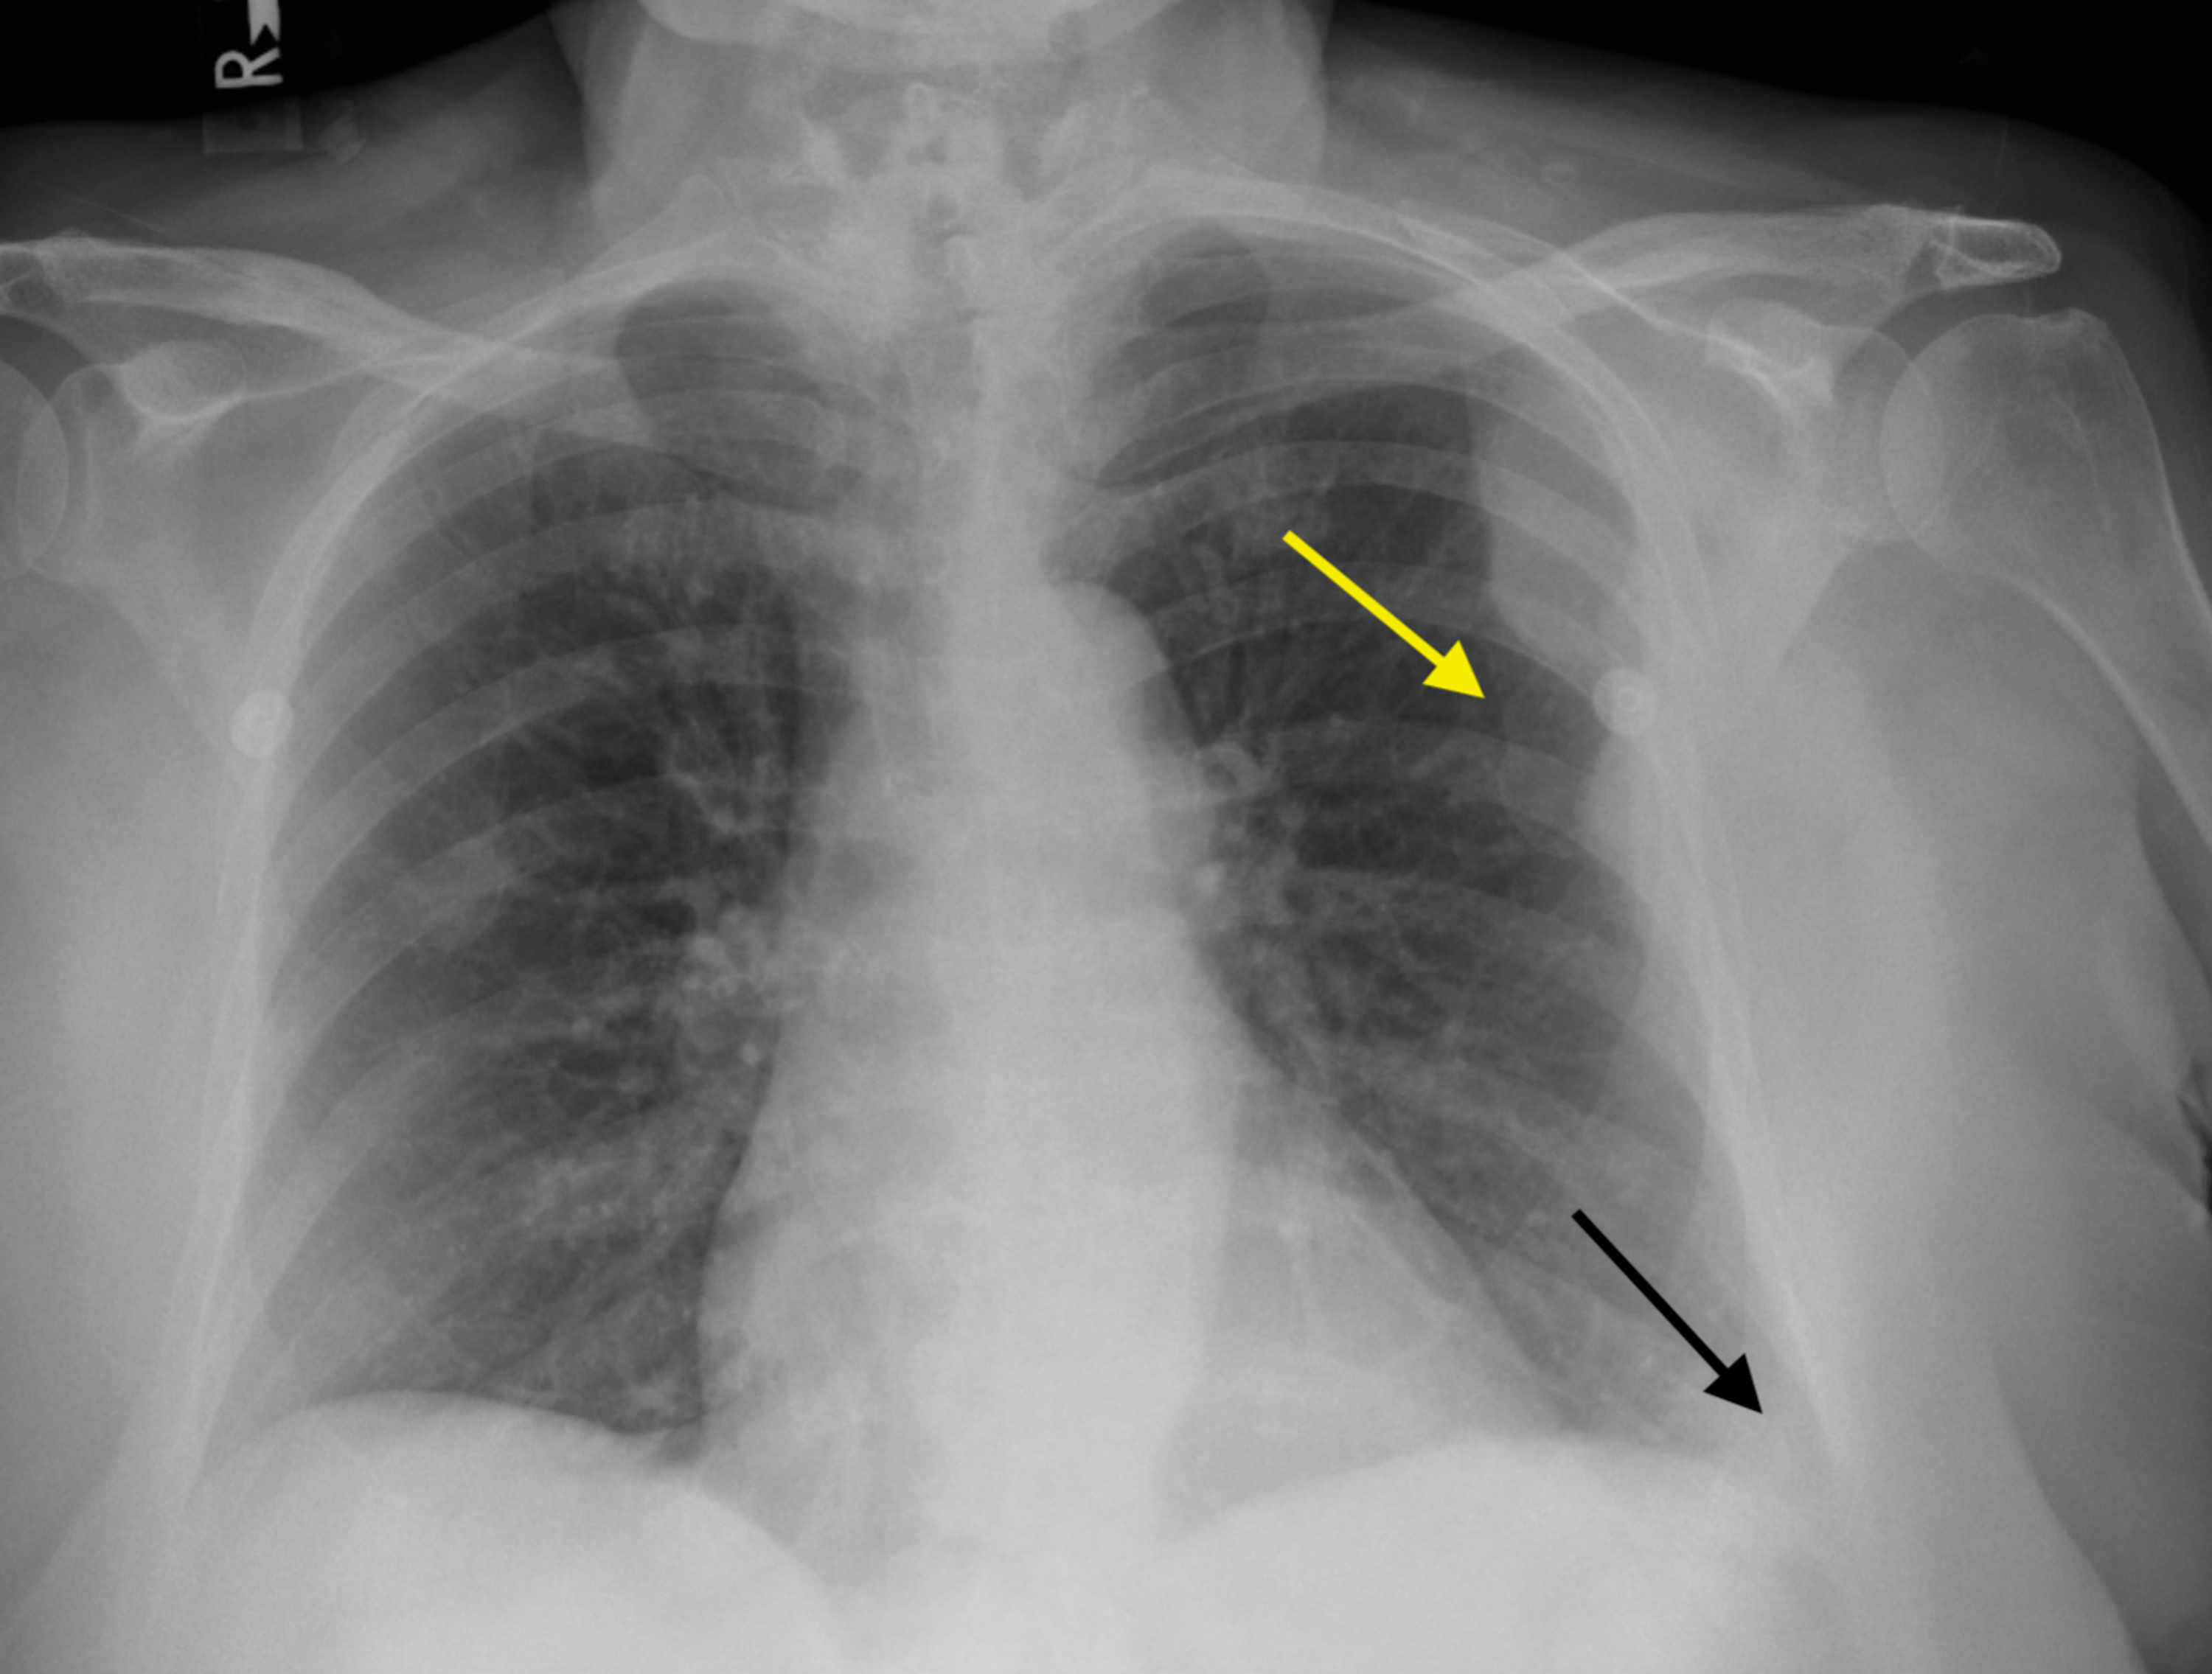

From pubs.sciepub.com

Figure 1. Posteroanterior chest Xray of patient showing right hilar Can A Chest X Ray Diagnose Lymphoma Lymphomas are malignancies that arise from mature lymphocytes. Lymphoma diagnosis often begins with an exam that checks for swollen lymph nodes in the neck, underarm and groin. The best way to diagnose lymphoma is to perform a biopsy of a lymph. To look for possible signs of lymphoma coming back after treatment; Patients with lymphoma often have ct scans of. Can A Chest X Ray Diagnose Lymphoma.